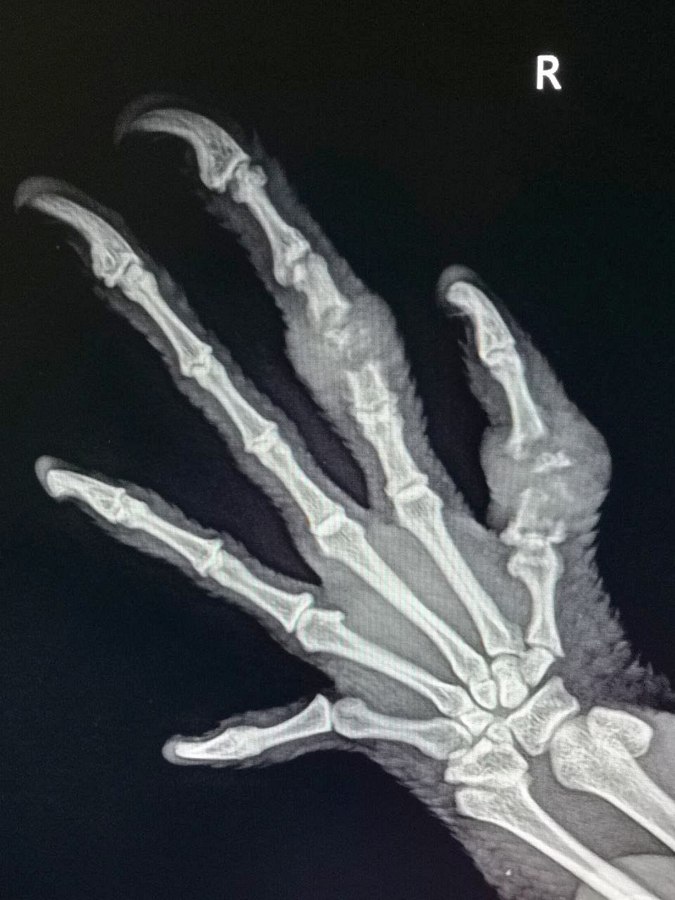

Игуана из Зеленограда сломала два пальца в «битве» с зеркалом

В государственной ветеринарной клинике в Восточной промзоне прооперировали экзотическую ящерицу, получившую травмы от столкновения с зеркалом.

О необычном случае в практике зеленоградских ветеринаров рассказали в пресс-службе «Мосветобъединения». В городскую ветклинику обратились владельцы полутораметровой 5-летней игуаны по кличке Изумрудик, столкнувшиеся со странным поведением своего питомца в период гона — игуана начала бросаться на свое отражение в зеркале, принимая его за соперника. Как выяснилось, во время «битвы» с зеркалом ящерица сломала два пальца. Но ее хозяева не сразу заметили травму и обратились к ветеринарам только через три недели после ее получения, когда отек и болезненность пальцев стали очевидными.

Срастить кости в данной ситуации было уже невозможно, и врачи приняли решение ампутировать поврежденные пальцы, чтобы избежать некроза. Игуану под газовым наркозом прооперировала хирург . «После ингаляционной анестезии питомцы просыпаются очень быстро, вот и Изумрудик, как только вышел из наркоза, продемонстрировал свою силу и мощь, пытаясь сбежать с операционного стола. Удержать такого дракона было совсем непросто», — рассказала ветеринар.